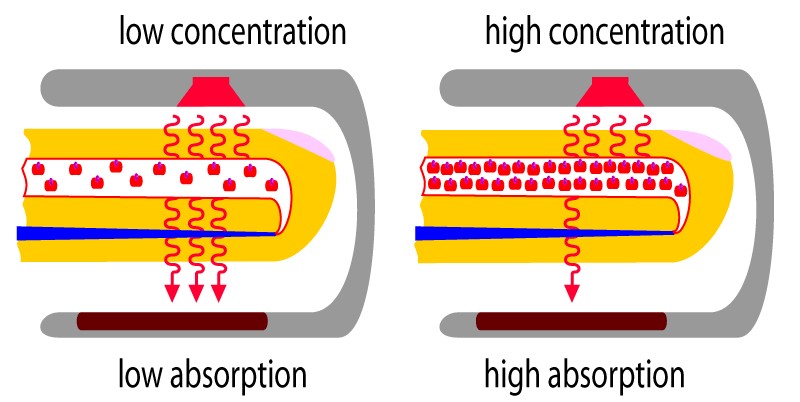

Hypoxemia – is a condition involving abnormally low blood oxygen levels. It can lead to bluish skin, difficulty breathing and fast heart rate. Apart from sleep apnea and higher altitudes, hypoxemia can be also be caused by many underlying illnesses, mainly lung and heart related especially in conditions of low environmental oxygen, diffusion impairment, hypoventilation, right -to left atrial shunting (image below).

Hypoxia – is a condition involving abnormally low levels of oxygen in body tissues. It can lead to bluish skin, confusion, difficulty breathing, restlessness and fast heart rate. Hypoxia is different to hypoxemia as hypoxia is low oxygen levels in tissues whereas hypoxemia is low oxygen levels in blood.

For distinction from neonatal respiratory distress syndrome, acute respiratory distress syndrome was also labelled as adult respiratory distress syndrome (ARDS). It involves inflammation in the lung parenchyma, increased alveolar permeability, reduced lung compliance and non-functional gas exchange. The increased alveolar permeability allows fluid to build up which in-turn prevents the lungs from filling up air, causing less oxygen in the bloodstream. The oxygen deprivation sequentially leads to organ failure. Low blood-oxygen levels in the bloodstream not only affects the lungs but, also harms other organs in the body and prevents oxygen from reaching them for normal functioning. The intensity of the disease can be determined by measuring and comparing blood-oxygen levels. ARDS is a rapidly developing and potentially fatal lung disease, most people don’t survive ARDS. ARDS survivors mostly have lasting damage to their lungs. The risk of death and the severity of the disease increases with age. The main symptom of ARDS is distressing shortness of breath, which develops within the first couple hours and lasts longer than the illness and the duration of recovery.

Type I: – involves a ventilation/perfusion mismatch that causes untreatable hypoxemia (PaO2). Another characteristic of type I respiratory failure is alveolar flooding.